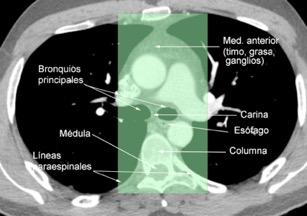

6. ÁREAS DEL MEDIASTINO EN TC

Tráquea y bronquios principales

Corazón/ Grandes vasos

Timo Conducto torácico

Esófago Ganglios Grasa Nervios

Medio: Saco pericárdico